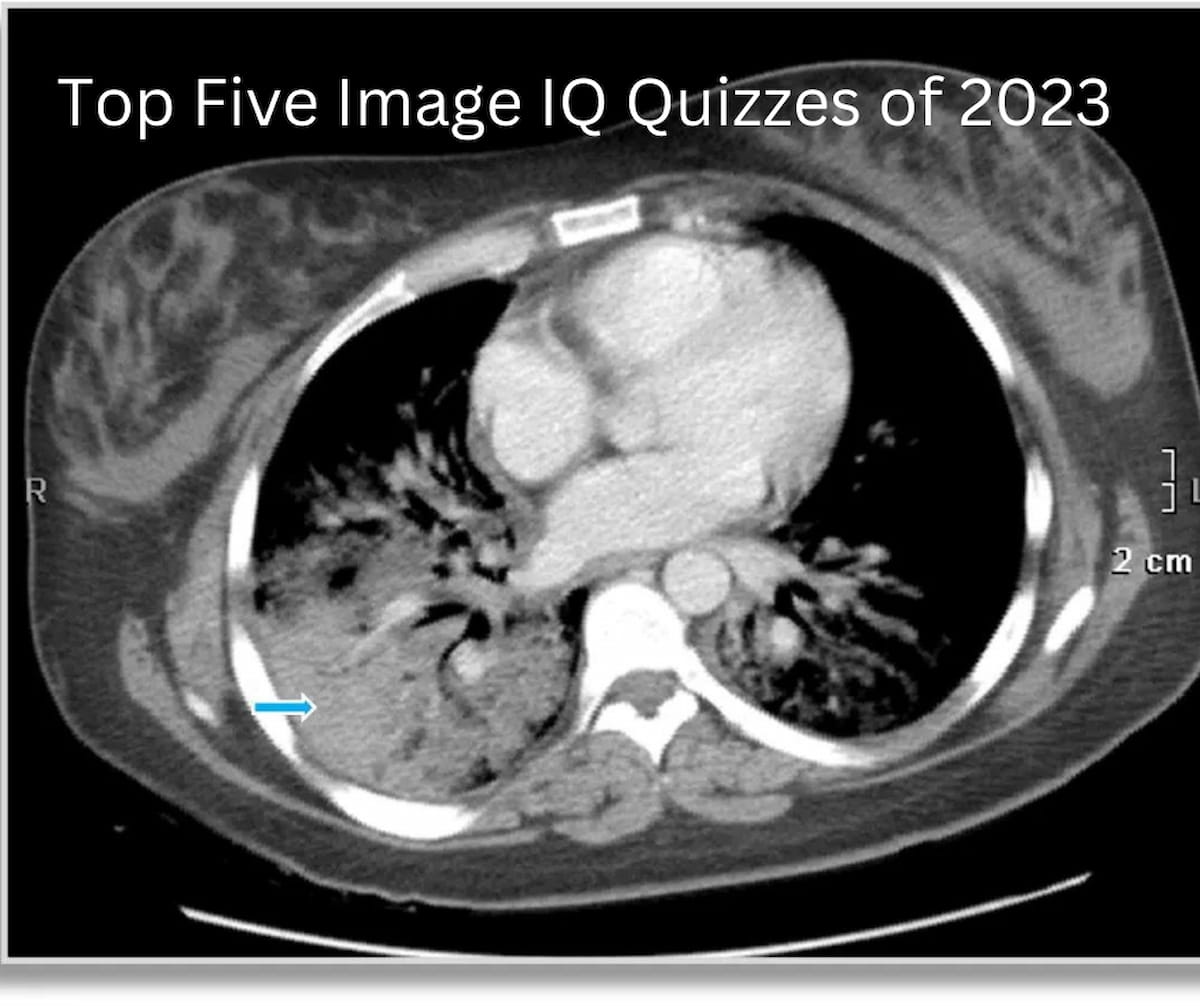

From www.diagnosticimaging.com

Diagnostic Imaging's Top Five Image IQ Quizzes of 2023 Diagnostic Radiology Lab Quiz How does a radiopaque structure appear on a radiograph? Study with quizlet and memorize flashcards containing terms like killivolts peak (kvp), milliamperes (ma), milliamperes/seconds. Study with quizlet and memorise flashcards containing terms like abdomen views, abdomen measurements, abdomen radiation field and others. Test yourself with the osce style scenarios and the radiology quiz questions. Case quizzes help improve healthcare education. Diagnostic Radiology Lab Quiz.